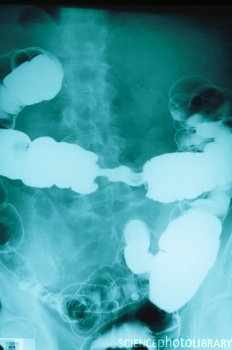

Диагностика рака толстой кишки имеет цель определить расположение опухоли, наличие местного или отдаленного распространения опухоли, оценить общее состояние пациента.

Для этих целей кроме осмотра применяются и инструментальные методы обследования (ректороманоскопия, рентгенологическое исследование толстой кишки – ирригография, колоноскопия, КТ, УЗИ).